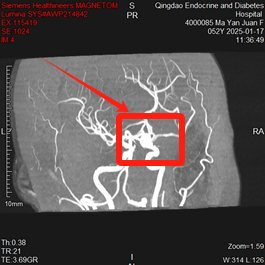

张女士自患糖尿病以来便很注重自身健康,会定期进行查体。最近,我院健康管理中心AI查体系统结合张女士上次检查时间、个人年龄等信息、专项诊疗方案、生活习惯、遗传等多方面因素,为其生成个性差异化的深度体检方案,方案中包含了头颅磁共振动脉成像检查。在检查过程中,医生在她的颅内发现了一个“不定时炸弹”——动脉瘤。这个消息如同一记重锤,让张女士及家人瞬间紧张了起来。但幸运的是,因为发现及时,张女士得以迅速接受专业治疗,解除了“静默威胁”。

三、磁共振:颅内动脉瘤的侦察兵

磁共振(MRI)是一种先进的医学影像技术,它在颅内动脉瘤的诊断中发挥着重要作用。通过磁共振检查,医生可以清晰地观察到脑部动脉的走行区,发现瘤样扩张、结节样的突出,从而确诊动脉瘤与其他检查方法相比,磁共振具有无创、无辐射、分辨率高等优点,能够更准确地评估动脉瘤的大小、形态和位置,为后续的治疗提供重要依据。